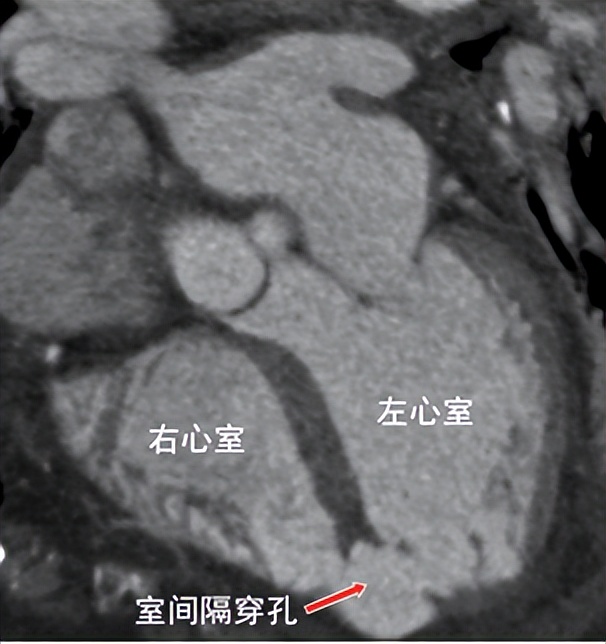

术前增强CT显示室间隔近心尖处穿孔

患者为92岁女性,入院前1周突发胸骨后闷痛,因胸痛程度不剧烈且症状自行缓解,误以为是胃肠道疾病,未予重视;后逐渐出现恶心、四肢乏力、气促、端坐呼吸等症状,由家属送至我院急诊科。急诊行心电图提示患者前壁心肌梗死,进一步完善心脏彩超见室间隔心尖段变薄、搏幅减低,探及大小约19mm回声失落,合并室间隔穿孔。